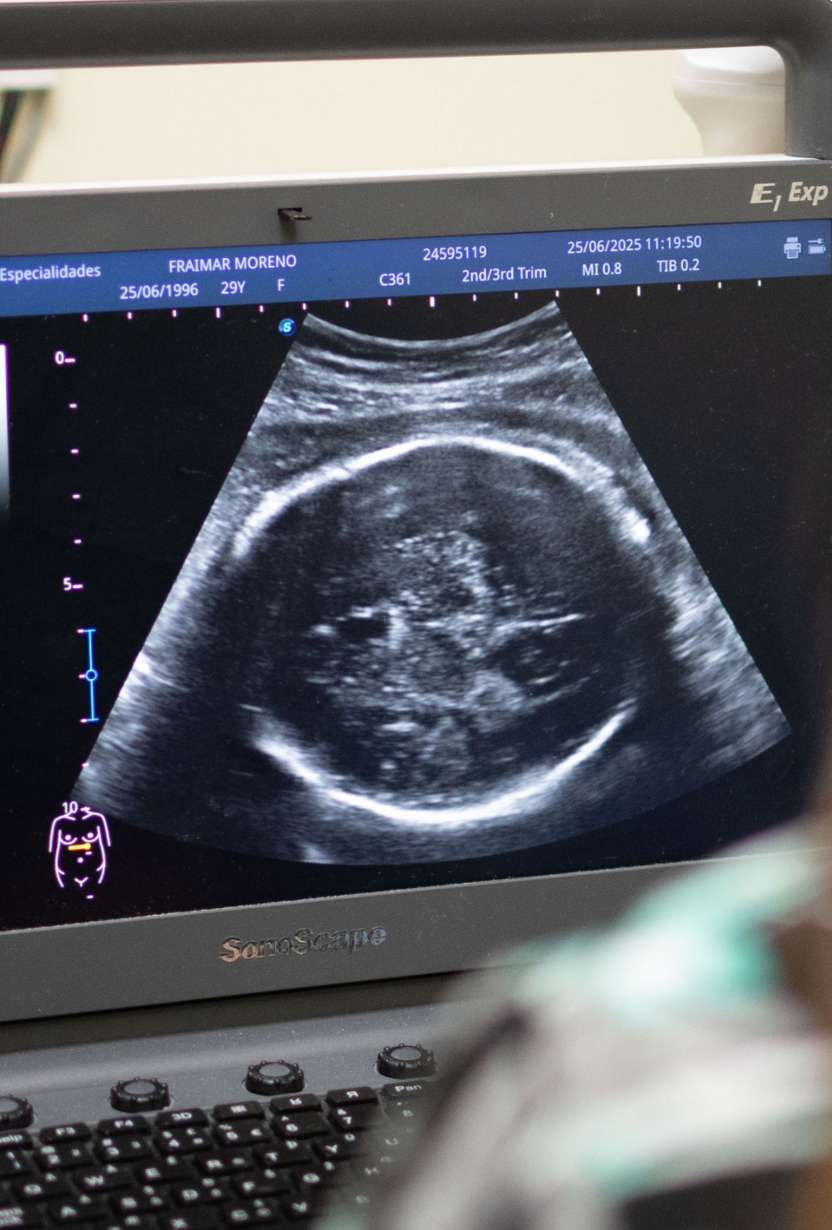

Unidad de Ecografía con equipo P20 sonoScape que permite realizar ecografías en hasta 5D.

En nuestra institución, contamos con una avanzada Unidad de Ecografía equipada con la tecnología más moderna del mercado, incluyendo el equipo P20 sonoScape, que permite realizar ecografías en hasta 5D. Este nivel de innovación nos posiciona como líderes en la prestación de servicios de diagnóstico por imagen en todas las especialidades médicas. Nuestro compromiso es ofrecer diagnósticos precisos y detallados, garantizando la máxima calidad en cada estudio realizado.